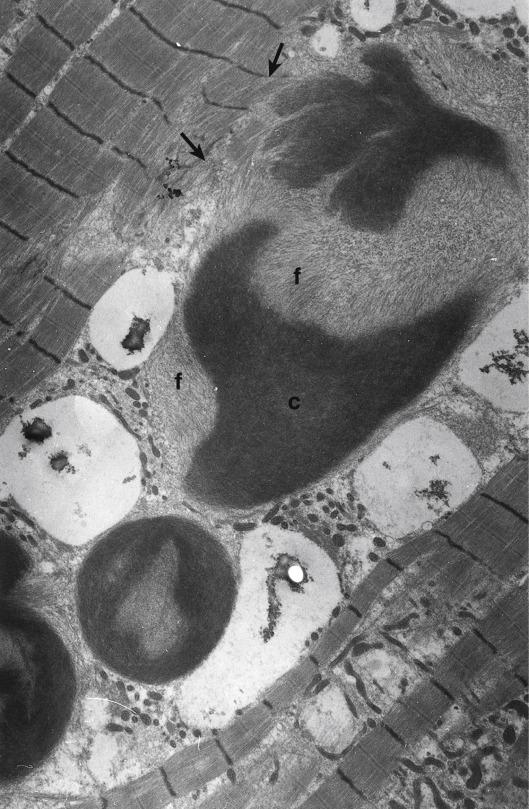

Cytoplasmic bodies are also thought to be an abnormality of the Z line and are characterized by a dense circular or oval centre and a peripheral zone of fine filaments radiating from it. Between the two zones, a pale halo of randomly orientated fine filaments is sometimes visible ( Fig. 5.40 ). The biochemical nature of the dark core is not fully known, but it is filamentous and sometimes shows structural continuity and shows similarities to the Z line; the radiating filaments resemble actin, and continuity with adjacent myofibrils is sometimes seen ( Fig. 5.41 ); also, desmin is seen in the halo ( ). Occasional cytoplasmic bodies may be found in many disorders where degeneration of myofibrils occurs and particularly where Z line abnormalities are common. They may occur singly within a fibre or in groups (see Fig. 5.41 ) and are easily visible with routine histological stains such as Gomori trichrome (see Ch. 4 ). Cytoplasmic bodies are quite common in some congenital myopathies, inclusion body myositis, reducing body myopathy and myofibrillar myopathies ( ). They can also be a feature in patients with TTN- associated hereditary myopathy with early-onset respiratory failure (HMERF) (see Ch. 16 ). Spheroid bodies structurally resemble cytoplasmic bodies and are associated with mutations in the gene encoding myotilin (see below and Ch. 15 ). ‘Cytoplasmic body neuromyopathy’ was described several years ago as a disease entity ( ), but it is also likely to be part of a clinical spectrum associated with a known genetic defect. Recently, cytoplasmic bodies have been noted to be a particular feature of cases with mutations in the skeletal α-actin gene ( ). A biopsy referred to us that contained numerous cytoplasmic bodies in the muscle was from a patient who habitually took senna.

Fig. 5.40, Cytoplasmic body with a dense core (dc) surrounded by a halo (h) and with filaments (f) radiating from it. Triads (tr) are prominent and a replicated triad (rtr) is present. (Spinal muscular atrophy.)

Fig. 5.41, Group of unusual cytoplasmic bodies which show continuity with myofibrils (arrows). The core (c) is irregular in shape and not circular; no halo is present, but filaments (f) radiate from the core. (‘Cytoplasmic body myopathy’.)